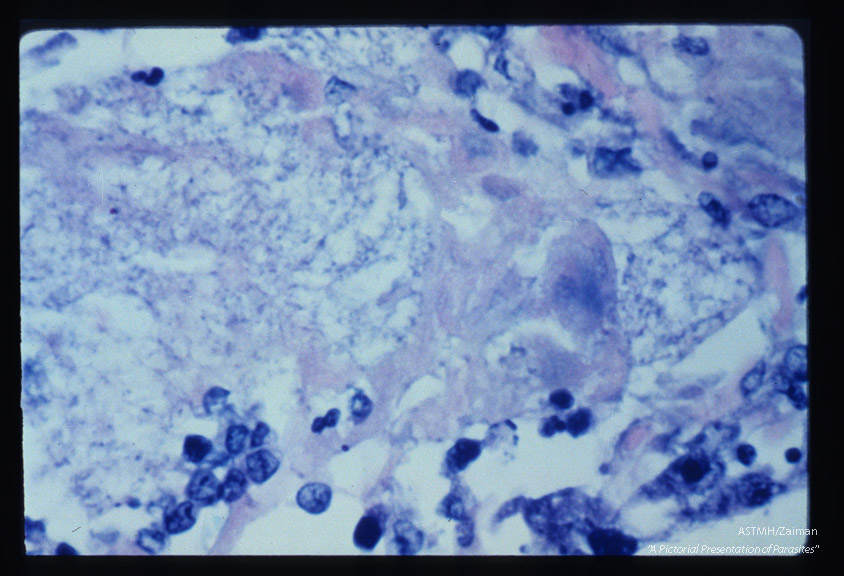

Pneumonia. Low power view of infected lung stained with silver methenamine. Some parasites stain better than others.

Pneumocystis carinii

Description: Pneumonia. Low power view of infected lung stained with silver methenamine. Some parasites stain better than others.